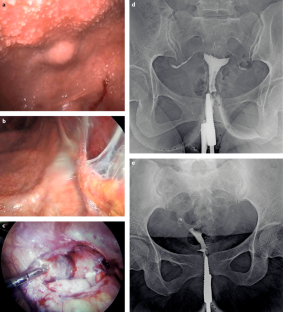

Mayilvaganan, K. R., Naren Satya Srinivas, M., Reddy, V. N. & Singh, R. K. Tuberculosis penis with ‘Watering can penis’ appearance: report of a rare case with retrograde urethrography and voiding cystourethrography findings. Pol. J. Radiol. 81, 454–457 (2016).

Ahmadi, F., Zafarani, F. & Shahrzad, G. Hysterosalpingographic appearances of female genital tract tuberculosis. I. Fallopian tube. Int. J. Fertil. Steril. 7, 245–252 (2014).

Ahmadi, F., Zafarani, F. & Shahrzad, G. S. Hysterosalpingographic appearances of female genital tract tuberculosis. II. Uterus. Int. J. Fertil. Steril. 8, 13–20 (2014).

Farrokh, D., Layegh, P., Afzalaghaee, M., Mohammadi, M. & Fallah Rastegar, Y. Hysterosalpingographic findings in women with genital tuberculosis. Iran. J. Reprod. Med. 13, 297–304 (2015).

A.Z. receives a UK National Institutes of Health Research (NIHR) senior investigator award. A.Z. acknowledges support from the PANDORA-ID-NET grant from the EDCTP Reg/Grant RIA2016E-1609), CANTAM2, TESA2 and EACCR2 EDCTP Networks of Excellence grants, all funded by the European and Developing Countries Clinical Trials Partnership (EDCTP2) programme, which is supported under Horizon 2020, the European Union’s Framework Programme for Research and Innovation. A.Z. and A.M. acknowledge support from the NIHR Biomedical Research Centre at UCLH. Figures 3a, 3b, 3c, 3d, 3i, 7c, 7d and 7e were kindly provided by Professor Sebastian Lucas, St Thomas’s Hospital, London.